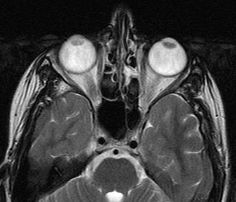

Технологии магнитно-резонансной томографии позволяют продвигать медицину вперёд. Данный метод за последние годы становится всё более популярным, а оборудование активно закупается различными клиниками. Врачи получают в руки мощный инструмент, позволяющий обнаруживать серьёзные проблемы в состоянии здоровья. Томография орбиты глаза используется для исследования и лечения отклонений зрения.

МР томография позволяет увидеть изменения в:

- мышцах глаза;

- глазном яблоке;

- жировой клетчатке;

- зрительных нервах;

- слезных протоках;

- ретробульбарном пространстве.

Метод основан на способности ядер водорода реагировать на воздействие радиомагнитной волны извне. Активность регистрируется компьютером, что позволяет моделировать трёхмерное изображение исследуемого органа. МР томография полностью безопасна и проходит безболезненно, но при этом специалисты получают достаточно информации для планирования дальнейшего лечения.

Конкретный вид диагностики выбирается в зависимости от того, какую именно информацию требуется получить. МРТ в данном случае представляется достаточно универсальным способом решения поставленной задачи. Главное достоинство метода заключается в том, что в ходе сканирования удаётся получить проекцию исследуемого органа в различных плоскостях. На трёхмерном изображении в натуральную величину уже намного легче выявить имеющуюся патологию.

В области глазницы располагается множество разных структур – нервы, сосуды, мышцы и многое другое. На сегодняшний день только с помощью МРТ можно достаточно точно определить их целостность, а также выявить те или иные изменения. С помощью этого метода томографии выявляются различные отклонения: